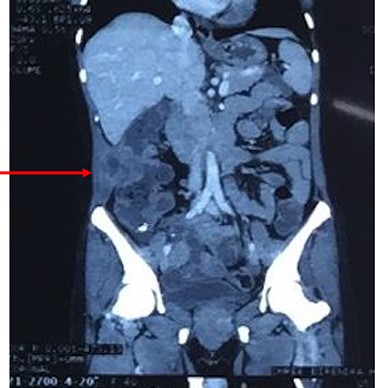

Coronal reconstruction of CT shows mass extending from colon and invading into anterior abdominal wall. Arrows indicate the point of exit of mass through the abdominal wall musculature.

Ascending colonic cancer complicated by an anterior abdominal wall abscess was diagnosed. Exploratory laparotomy was performed and a right colonic mass ~9 × 8 cm in diameter was found, which was widely adherent to the lateral abdominal wall, with extension through a fistulous track into the subcutaneous tissue (Fig. 4). There was no distant metastasis. Extended right hemicolectomy and lymph node dissection was performed with limited resection (en bloc) of the involved part of the lateral abdominal wall using a closure technique.